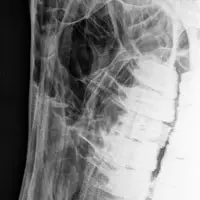

Die Anwendungsbereiche für röntgenologische Untersuchungen sind sehr vielfältig. Fast jede Lahmheitsuntersuchung und orthopädische Untersuchung erfordert die röntgenologische Darstellung bestimmter Gliedmassenabschnitte in mehreren Ebenen. Nahezu jede Kaufuntersuchung beinhaltet neben der klinischen Untersuchung auch die Erstellung von Röntgenbildern der Gliedmaßen und in vielen Fällen auch der Oberlinie. Bei bestehenden Rittigkeitsbeschwerden wird häufig eine Röntgenuntersuchung des Halses und des Rückens vorgenommen. Aufgrund der Leistungsstärke unserer Röntgenanlagen ist es uns häufig möglich, auch den Beckenbereich des Pferdes inklusive Hüftgelenk am stehenden Pferd zu untersuchen.

Ebenfalls besteht bei Zahnerkrankungen oder Erkrankungen des Schädels die Möglichkeit der röntgenologischen Untersuchung. Dieses beinhaltet auch die Darstellung der Kiefer- und Stirnhöhle sowie der Schneide- und Backenzähne. Bei Lungenerkrankungen tragen Röntgenaufnahmen der Lunge zur Diagnosefindung bei. Darüber hinaus werden in unserer Klinik spezielle Röntgenverfahren mit Kontrastmittel bei Verdacht auf Ataxie (Myelographie) oder Weichteilerkrankungen der Gelenke (Arthrographie) durchgeführt. Im Rahmen der Therapie wird das Röntgen unterstützend zur zielgenauen Injektion von Medikamenten eingesetzt.